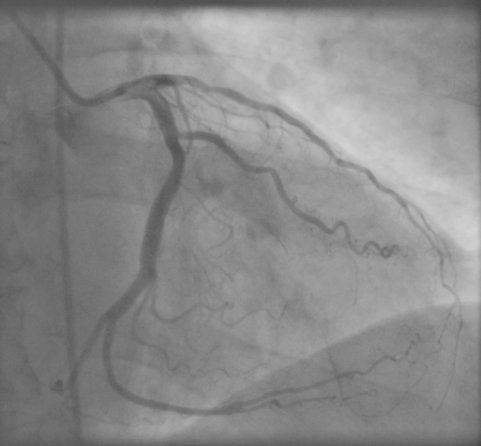

Coronary Angiogram |

Alternatively we can use conventional fluoroscopic X-ray

angiography, which provides high-resolution 2D projections of the

coronary arteries. Two or more such projections can be used to

create a 3D model of the vessel tree if the relative projections

are known and the different arteries can be identified in both

projections.